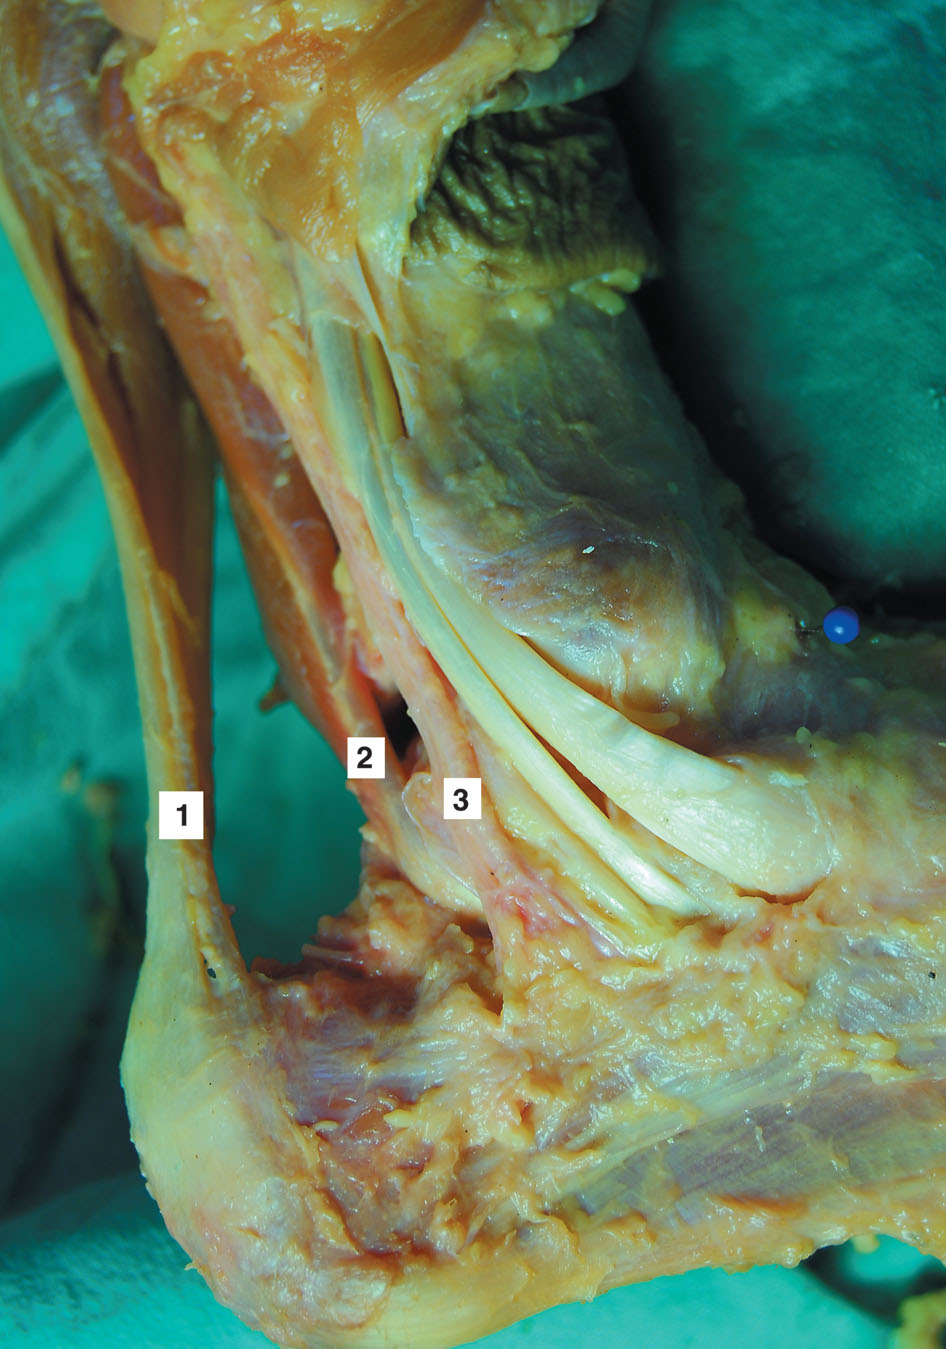

Figura11: Preparado anatómico de 1) Tendón de Aquiles,2) Tendón del flexor largo del hallux y 3) Paquete vasculonerviosotibial posterior.

Se realiza inmediatamente medial al tendón de Aquiles y a la misma altura del posterolateral. Al igual que el portal posterolateral sólo se incide piel y con una pinza roma se toca en forma perpendicular la camisa del artroscopía, ya en el portal posterolateral. Las estructura en riesgo en este portal es el paquete vasculonervioso tibial posterior que se encuentra adelante del tendón flexor largo del hallux (Fig 11). Luego se introduce la punta del sistema motorizado a utilizar, se recomienda de pequeño calibre (3 mm) y se desliza tocando la camisa del artroscopio hasta alcanzar la parte posterior de tobillo. Con precaución se resecan tejidos blandos: grasa periarticular y ligamento de Rouviére y Canela, y se busca el tendón del flexor largo del hallux (Fig. 12) que sería en el tobillo posterior la estructura a reconocer para trabajar sin riesgo de lesionar el paquete vasculo nervioso tibial posterior que como mencionamos

se encuentra por delante de este tendón. Es útil movilizar el hallux para ver como excursiona el tendón con su vientre muscular y visualizarlo más rápido y mejor. Trabajos de estudios de investigación anatómicos como los de Sitler y Lijoi sugieren que los portales posterolateral y posteromedial cercanos al tendón de Aquiles y proximales al maléolo peróneo son seguros para acceder al tobillo posterior (18, 19, 20, 21, 22, 23).